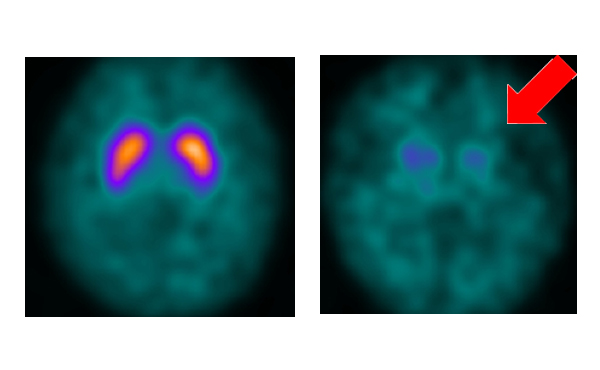

ドパミントランスポーターシンチ

パーキンソン症候群やレビー小体型認知症の診断等に行われる検査です。赤白っぽい色で、形が大きいとドパミントランスポーターの数が多く、青色で形が小さいとドパミントランスポーターの数が少なくなります。